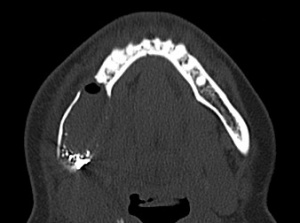

In einer extern angefertigten Panoramaschichtaufnahme bestand eine im Bereich apikal der Zähne 44-47 liegende und bis unterhalb des Processus condylaris reichende, ausgedehnte, mehrkammerige, scharf begrenzte Aufhellung. In direkter Lagebeziehung mit dem zystischen Prozess stellte sich apikal des Zahnes 46 der retinierte und verlagerte Zahn 45 dar.

Anamnestisch handelte es sich bei dieser Röntgenaufnahme um die erste Panoramaschichtaufnahme, die jemals bei dem Patienten angefertigt wurde (Abbildung 1).

Ein ergänzend durchgeführtes Denta-CT des Unterkiefers (Abbildungen 2 und 3) zeigte eine zystische Raumforderung im Bereich der rechten Unterkieferhälfte, welche bis weit in den aufsteigenden rechten Unterkieferast reichte. Der Nervkanal des rechten N. mandibularis verlief durch die Raumforderung und ließ sich nicht sicher abgrenzen.